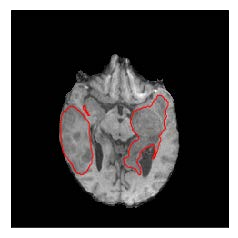

Machine learning has been widely adopted for medical image analysis in recent years given its promising performance in image segmentation and classification tasks. The success of machine learning, in particular supervised learning, depends on the availability of manually annotated datasets. For medical imaging applications, such annotated datasets are not easy to acquire, it takes a substantial amount of time and resource to curate an annotated medical image set. In this paper, we propose an efficient annotation framework for brain MR images that can suggest informative sample images for human experts to annotate. We evaluate the framework on two different brain image analysis tasks, namely brain tumour segmentation and whole brain segmentation. Experiments show that for brain tumour segmentation task on the BraTS 2019 dataset, training a segmentation model with only 7% suggestively annotated image samples can achieve a performance comparable to that of training on the full dataset. For whole brain segmentation on the MALC dataset, training with 42% suggestively annotated image samples can achieve a comparable performance to training on the full dataset. The proposed framework demonstrates a promising way to save manual annotation cost and improve data efficiency in medical imaging applications.

翻译:近年来,由于在图像分割和分类任务方面表现良好,医学图像分析广泛采用了机器学习。机器学习的成功,特别是监督学习的成功,取决于手动附加说明数据集的可用性。对于医疗成像应用来说,这种附加说明数据集不容易获得,需要大量的时间和资源来翻译附加说明的医学成像集。在本文件中,我们建议为大脑MR图像建立一个高效的注释框架,为人类专家提供信息性样图像,供人类专家作说明。我们评估了两种不同的大脑图像分析任务的框架,即脑肿瘤分割和整个大脑分割。实验显示,对于BRATS 2019数据集的脑肿瘤分割任务,培训一个只有7%的附加说明图像样本的分解模型,其性能与全数据集培训的性能相当。对于MALC数据集的整个大脑分割,用42%的附加说明性图像样本进行的培训,可以实现与全数据集培训的类似性能。拟议的框架展示了节省人工注解成本和提高医疗成像应用数据效率的有希望的方法。